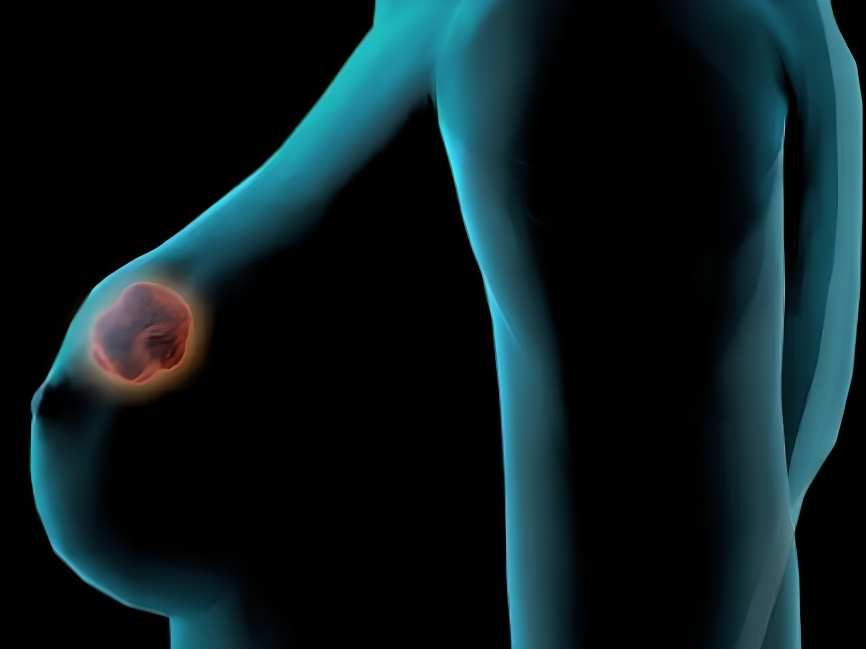

Reino Unido. – Un innovador enfoque terapéutico para el cáncer de mama asociado a mutaciones BRCA1 y BRCA2 ha demostrado resultados sin precedentes en un ensayo clínico internacional: ninguna de las 39 pacientes tratadas con este protocolo falleció durante los tres años de seguimiento. La investigación, liderada por la Dra. Jean Abraham del Addenbrooke’s Hospital y la Universidad de Cambridge, podría redefinir el estándar de cuidado para estos casos particularmente agresivos.

El estudio Partner probó una estrategia distinta: administrar quimioterapia seguida de olaparib (comercializado como Lynparza) con un intervalo de 48 horas antes de la cirugía, en lugar del esquema convencional que usa el fármaco solo después de la operación. La diferencia fue contundente: mientras el grupo de control con quimioterapia tradicional registró seis muertes entre 45 pacientes, el grupo experimental mantuvo supervivencia total. «Esto podría convertirse en el nuevo estándar de tratamiento», afirmó la Dra. Abraham.

Cabe señalar, que el olaparib, un inhibidor de PARP ya aprobado en múltiples países, demostró mayor eficacia cuando se administró durante solo 12 semanas preoperatorias, reduciendo costos y efectos secundarios comparado con el año de tratamiento postoperatorio habitual. La clave estuvo en el intervalo de 48 horas entre terapias, idea que surgió de una conversación informal entre la Dra. Abraham y el científico Mark O’Connor de AstraZeneca. Este breve período permite la recuperación de la médula ósea mientras aumenta la vulnerabilidad del tumor.

Michelle Mitchell de Cancer Research UK destacó el potencial traslacional: «Esta investigación demuestra que, con los tratamientos que ya tenemos, bien usados, podemos salvar más vidas». El protocolo, probado en 23 centros británicos, es particularmente relevante para sistemas de salud como el argentino, donde el medicamento ya está disponible sin requerir infraestructura especializada.

Testimonios como el de Jackie Van Bochoven reflejan el impacto humano: «Pensé en mis hijos, en mi hermana, en mi mamá… todas pasamos por esto. Hoy estoy bien, disfruto de cada día». La próxima fase del estudio evaluará la aplicación en otros cánceres BRCA+, incluyendo ovario, páncreas y próstata, buscando extender los beneficios de este enfoque secuencial que combina ciencia rigurosa con innovación accesible.